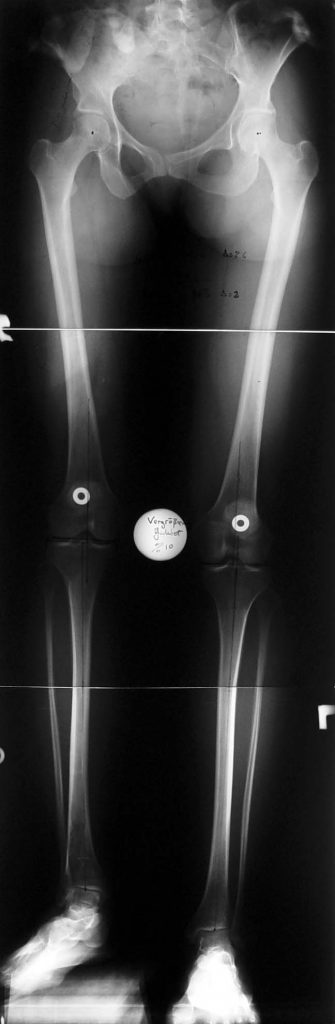

Case 2